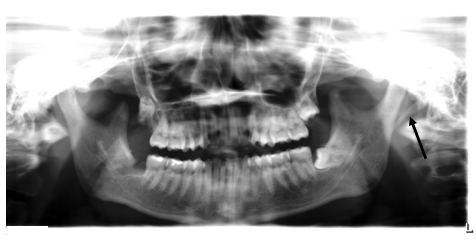

65.

箭頭所指柱狀放射線不透光之影像為何? (A) styloid process (B) osteoma (C) fracture (D) odontoma